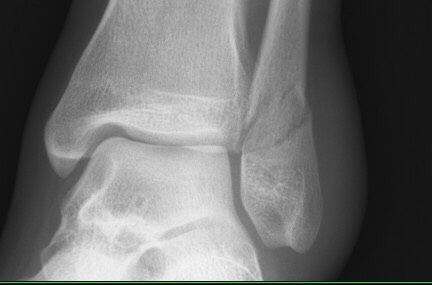

長這樣

第一眼看到我跟舅媽都愣了一下,因為原本的裂痕好像有點無法辨識出來,變糊了

所以這樣就是醫生說"裂痕變淡"了吧